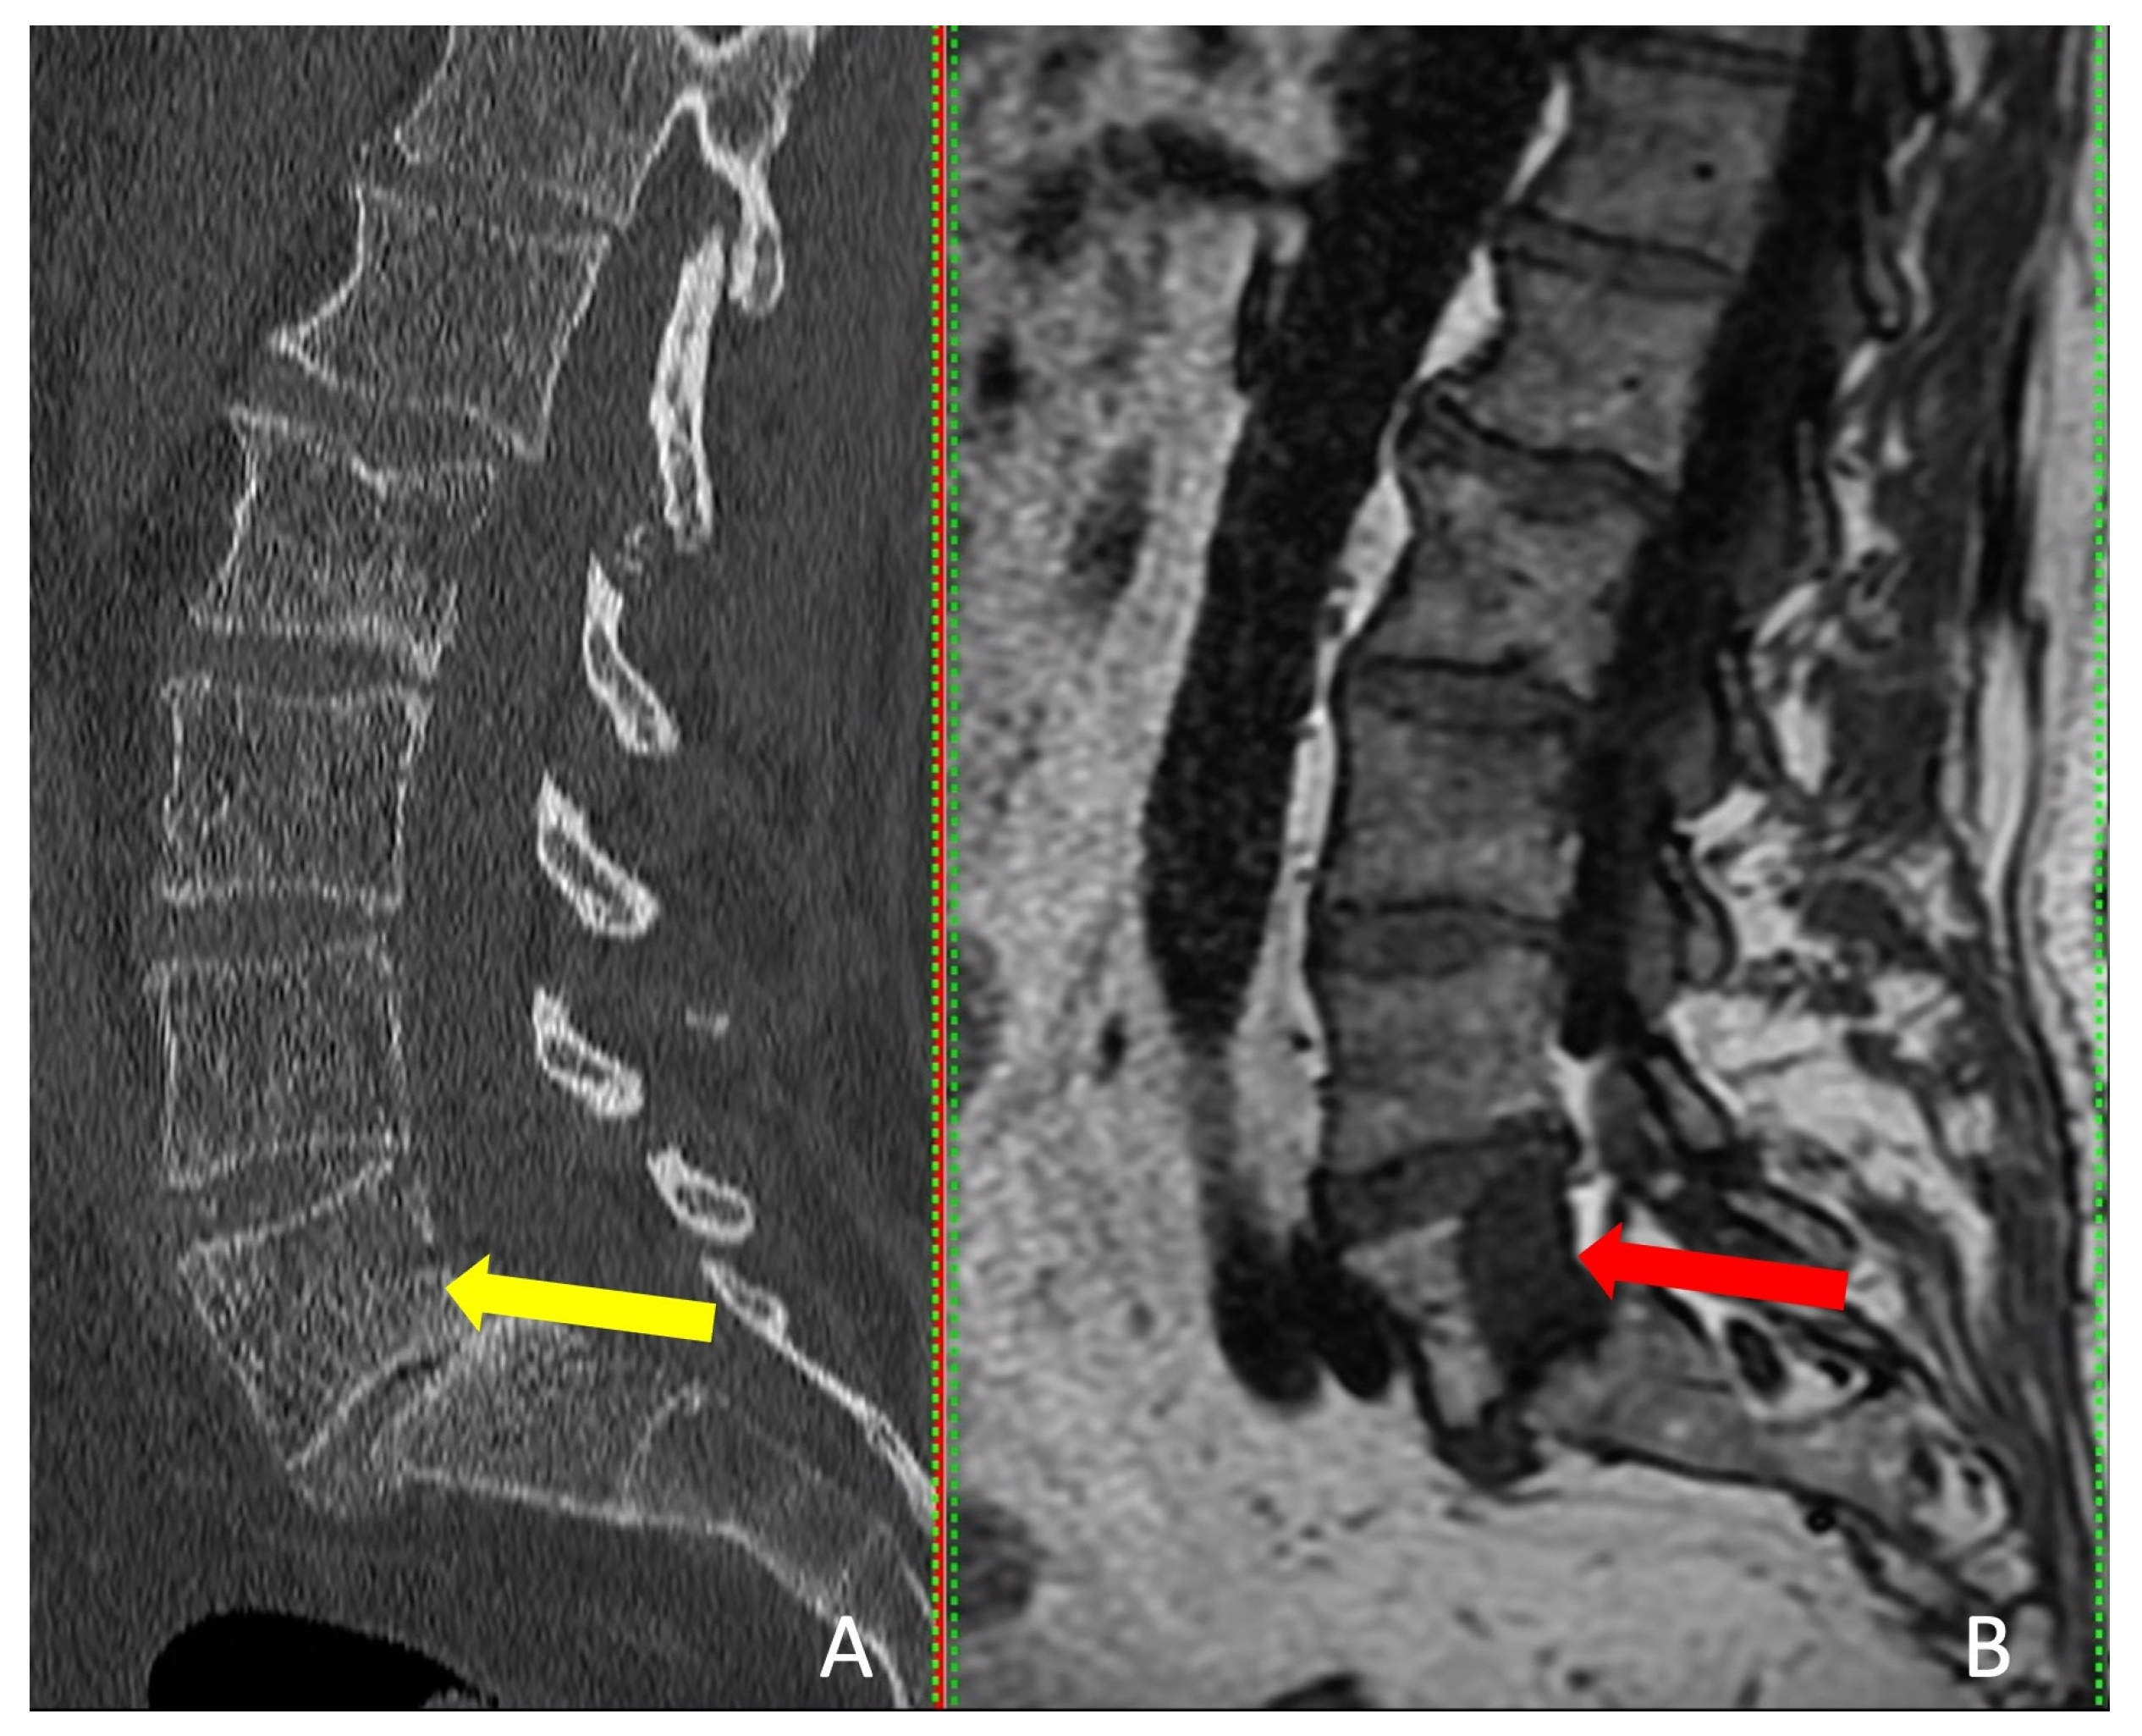

Interestingly, the tumor was visible on CT in only one patient, but MRI provided more accurate tumor dimensions (Table 2). MRI successfully revealed the tumors in all four patients (Figure 4). These patients presented with localized pain that did not radiate to the legs.

Figure 4. Sagittal view of CT scan (A) and MRI scan (B). The red arrow indicates the tumor and the yellow arrow shows where the tumor should be detectable.